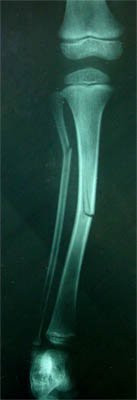

Greenstick fracture in tibia occurs while landing on foot in fall from height or due to blow to leg. But the force required for causing fracture to the tibia is higher than the force causing fracture in radius and ulna. The common sites of fracture are middle third and lower third of shaft of tibia.

Fig 5: Greenstick fracture of tibia and fibula